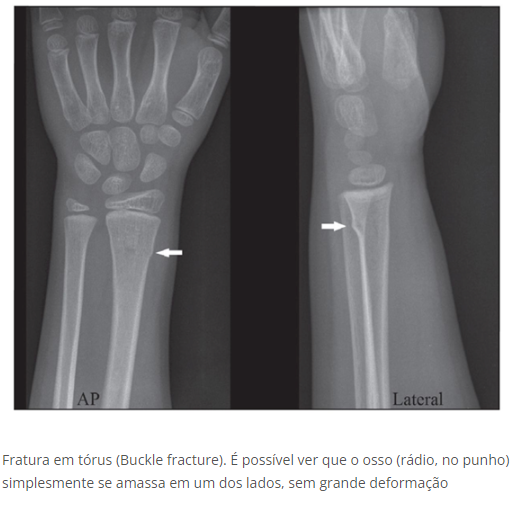

Fratura em Tórus/Fivela

• Há compressão do osso, mas sem deformação